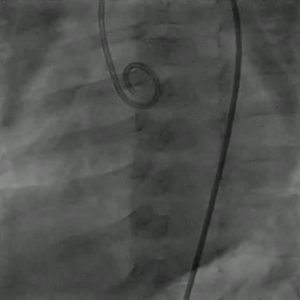

通过5F左冠造影管将0.032 in超滑导丝260 cm通过瘘口,进入下腔静脉后,使用网篮抓捕导丝建立轨道。

图片